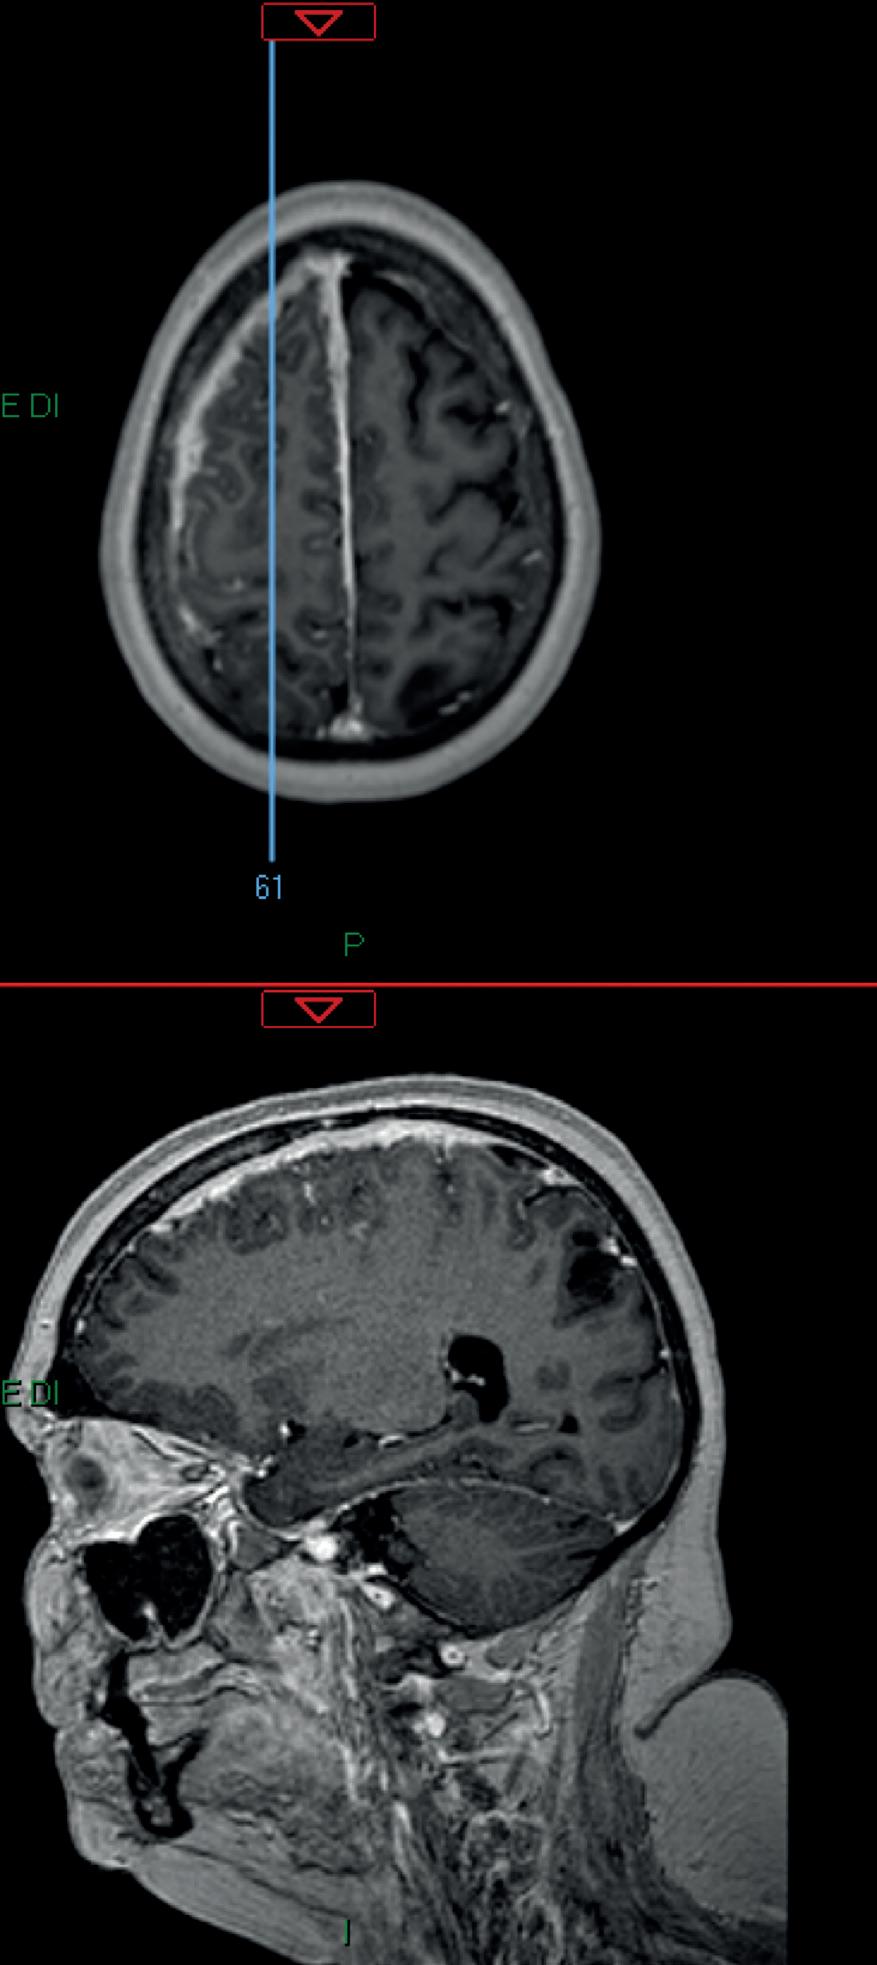

Figura 1. Esteso ispessimento e potenziamento leptomeningeo in sede frontale e parietale destra, specie al vertice con ispessimento durale diffuso (circa 6 mm) che attualmente si estende a interessare anche la grande falce cerebrale (con spessore max di circa 4 mm in sede anteriore). Permangono gli ispessimenti focali a carattere pseudonodulariforme in particolare a livello del giro frontale medio (diam. di 11 mm) nonché in sede occipitale destra.

ner”, cui segue la prescrizione di una terapia con enoxaparina sodica (4000 UI/die per un mese), golimumab (50 mg) e MTX (15 mg/sett), senza beneficio. Agli inizi di maggio 2016, il quadro si complica ulteriormente, con la comparsa di un’intensa, persistente e diffusa cefalea in regione sopraorbitaria e al movimento dei bulbi, che costringe la paziente a un ricovero in ambiente internistico. Sospesa la terapia farmacologica, durante la degenza vengono ripetuti gli esami di laboratorio e confermati nuovamente sia l’incremento degli indici di flogosi sia la presenza di lieve anemia. Viene anche eseguita RMN dell’encefalo (20/05/2016), con riscontro di piccole aree di alterato segnale a carico della sostanza bianca fronto-parietale, corone radiate bilateralmente in regione periventricolare frontale sinistra a distribuzione sottocorticale (da riferire a gliosi) e una piccola alterazione dell’intensità di segnale in regione temporale profonda sinistra (da riferire a cisti della fessura corioidea). Somministrato un mezzo di contrasto, si documenta anche una diffusa e discreta pachimeningite in assenza di aree nodulari e un sistema ventricolare simmetrico, in asse e normoampliato (Figura 1)